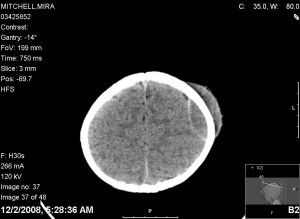

Dr. Robinson came in to talk with us more about the surgery and took us in to see the cat scan that had them concerned. For those that don’t know, think of a cat scan as a series of pictures that take different slices of your head to see what is going on. This is one of the slides that concerned us the most:

On the right hand side of the head, you can see the “perfect B cup” that Erika talked about. But just below that, you can see the epidural hematoma. If you look just above the injury inside the skull, you will see a small dart spot (that’s space). Which means this injury is actually putting pressure on her brain. Dr. Robinson told us that this is probably one of the biggest hematomas she has seen without accompanying symptoms. She couldn’t believe that Mira was just acting normal. This one picture was enough to convince us that we needed surgery.